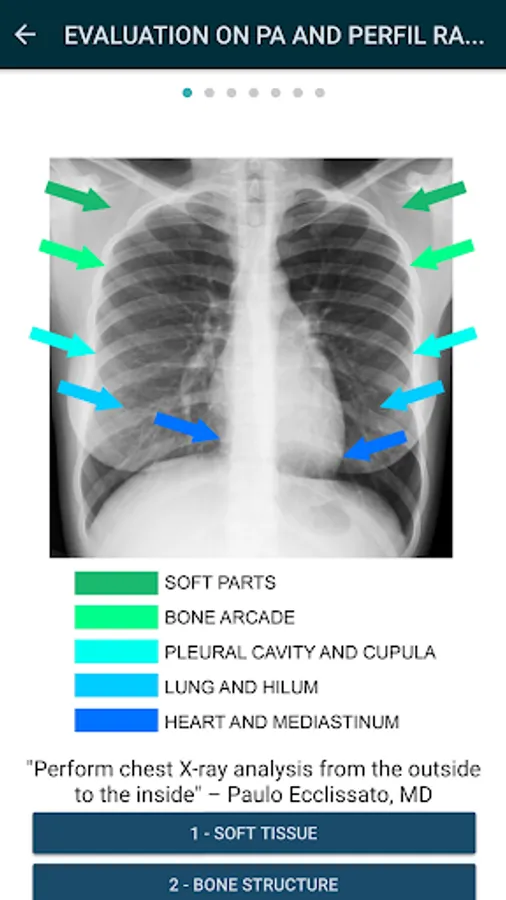

With a unique view of the most peripheral structures of the thorax to the most central, this method of interpretation allows a global and detailed evaluation.